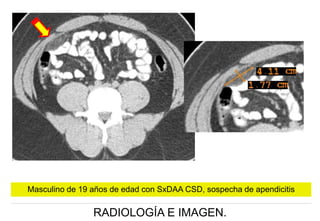

Masculino de 19 años de edad con SxDAA CSD, sospecha de apendicitis

Imagen coronal y axial TC , donde se observa aumento del tamaño de la

cabeza del páncreas con densidad homogénea.

Masculino de 64 años de edad con SxDAA CSD y sindrome icterico